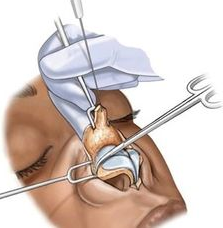

Burun Estetiği Açık Teknik

Kişisel tecrübeme gelince ameliyat sonrası şişliklerin daha az olması, dokuları daha az travmatize etmesi gibi düşüncelerle ilk planda kapalı tekniği tercih etmekteyim. Ancak hastanın burun deformitesi özellikle burun ucuna yönelik ağırlıktaysa veya çok detaylı bir cerrahi girişim yapılacaksa açık tekniği tercih etmekteyim. Ancak tecrübelerime göre kapalı teknik ile açık tekniğe gerek kalmadan bir çok hastanın sorunu çözülebilmektedir.